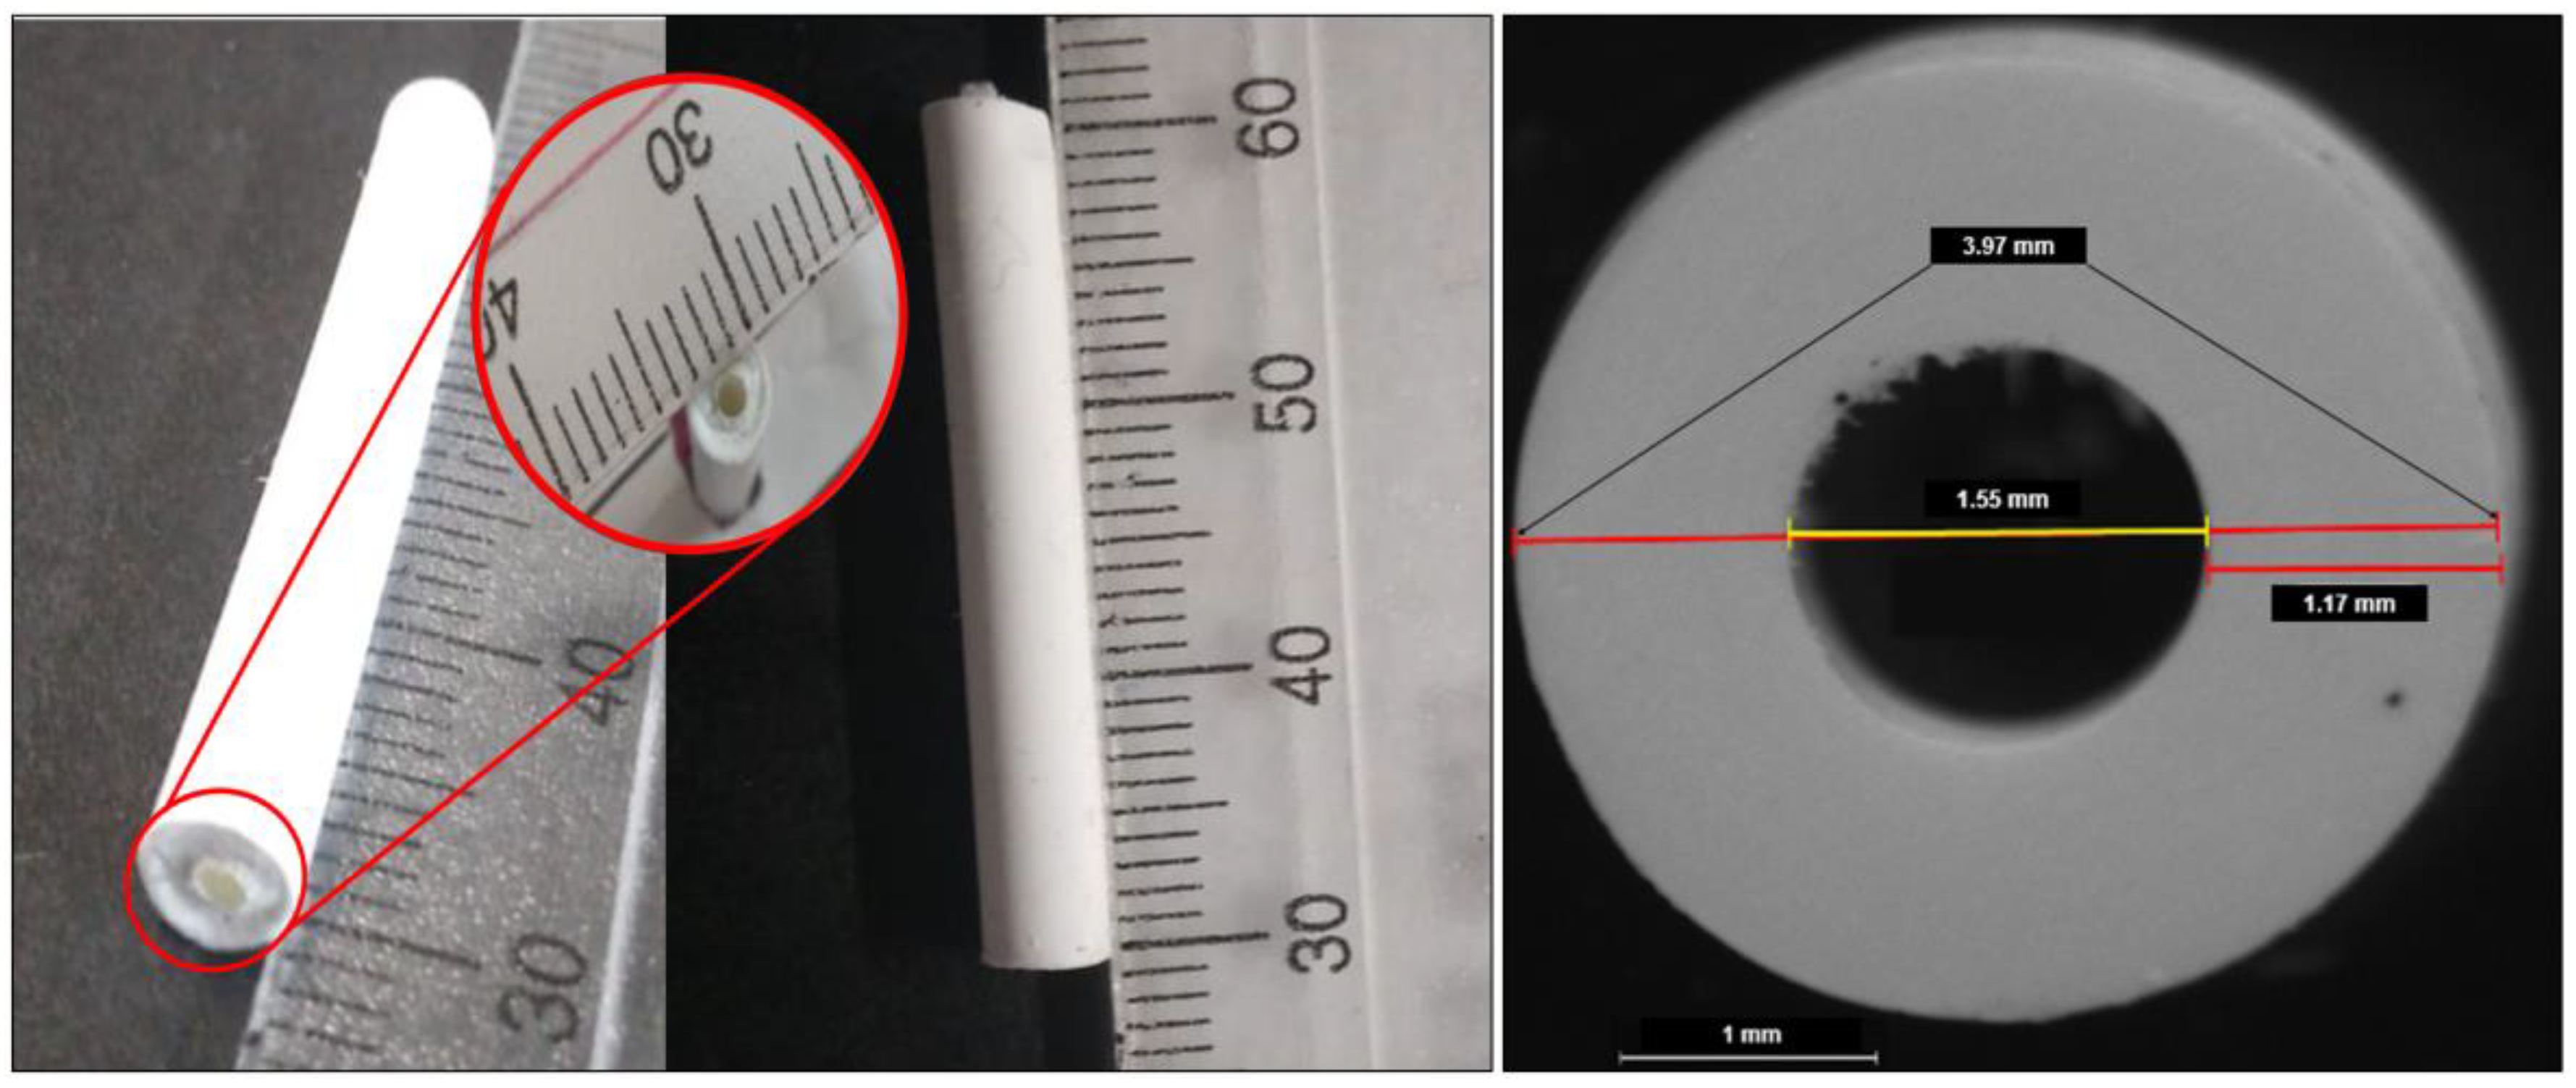

3.1.1. Drug Content Uniformity and Segment Geometry

3.1.2. Segment Degradation

| Formulation | Diameter (mm) | Theoretical Loading % | Drug Content (% ± SD) | Incorporation Efficiency (% ± SD) |

| N1 | 3.84 ± 0.006 | 5 | 4.99 ± 0.07 | 99.81 ± 1.36 |

| N2 | 3.73 ± 0.020 | 10 | 9.98 ± 0.1 | 99.77 ± 1.01 |

| N3 | 3.79 ± 0.080 | 5 | 5.00 ± 0.12 | 100.01 ± 2.33 |

| N4 | 4.11 ± 0.050 | 10 | 10.03 ± 0.22 | 100.36 ± 2.15 |

| N5 | 3.99 ± 0.076 | 7.5 | 7.51 ± 0.13 | 100.07 ± 1.75 |

| N6 | 4.03 ± 0.021 | 7.5 | 7.50 ± 0.39 | 99.98 ± 5.24 |

| N7 | 4.02 ± 0.012 | 7.5 | 7.48 ± 0.23 | 99.74 ± 3.01 |